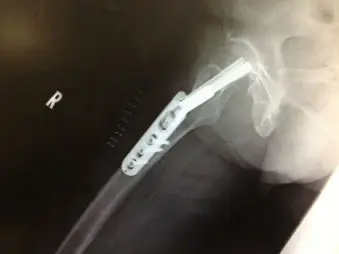

著しい疼痛があるもレントゲンで異常を認めない場合は、骨挫傷や不全骨折(亀裂骨折、若木骨折、竹節骨折)、疲労骨折などの不顕性骨折を認めることがある。不顕性骨折は骨梁の連続性は絶たれているが、骨膜の連続性は保たれているため、レントゲンやCTで異常所見を認めないことが多く,MRI T1強調像で低輝度を呈することによって診断される。外傷後や高齢者でレントゲン上明らかな骨折がないにも関わらず疼痛が持続する場合には、不顕性骨折を疑い、数日後、受傷1週間後のレントゲン再検査や、適宜CTやMRIを施行することが必要である。不全骨折はCTで骨折が判明することもあるが、骨挫傷に関してはCTで有意な所見を認めないことが多く、MRIが最も有用である。また、レントゲンでは骨梁の修復反応により、継時的に骨硬化像を認めるようになる。 全症例にMRIを施行することは困難なことがあり、高齢者の転倒を診る時にはレントゲンでは検出されない骨折があることを念頭に置き、患者にもその旨を説明の上、適宜、レントゲン再検査することが重要である。

左大腿骨頸部骨挫傷の他症例

CT像で転子部に骨折線とMRI T1強調像で同部位に低輝度を示す骨折線を認める